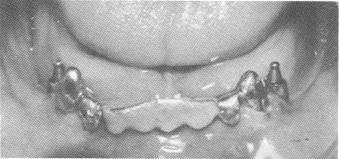

13-4b. The pins were fused to each other and locked between the inverted bar and template with cold cure acrylic. When the acrylic hardened it was prepared so that no undercuts remained. The vertical acrylic bar was then polished.

template (Fig. 13-43). These pins were extended deep into the bone, down to the cortical plate in the inferior portion of the mandible. The three pins were shortened to the height of the horizontal portion of the U-shaped bar (Fig. 13-44) and then bent anteriorly so that they fitted flush to, but underneath, the horizontal bar (Fig. 13-45). The three pins were fused together (using the brush-on technique) and to the entire inverted U-shaped bar with cold cure acrylic, thereby becoming an integral part of the template (Fig. 13-46). An all-acrylicover-gold full arch denture was then processed (Fig. 13-47). The bridge was used as a fixed removable denture and was set buccal to the mylohyoid ridge, instead of on it, to avoid further pain (Fig. 13-48). A Panorex shows the implants and prosthesis (Fig. 13-49) .

4 Dental pins fused & locked between inverted bar & scalloped template